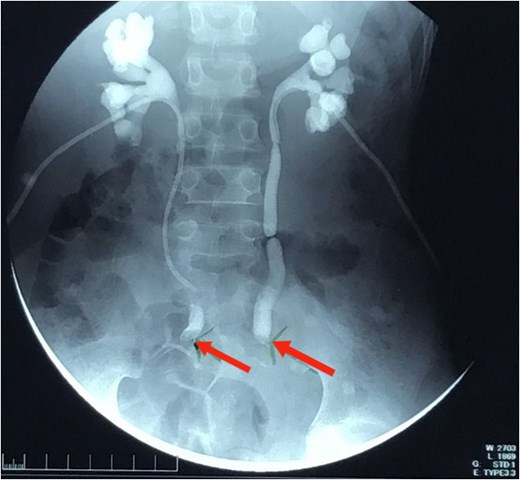

Pelvic MRI (Fig. 2) identified a 5.5 × 5.5 cm rectal mass invading the posterior wall, extending to the upper rectum and rectosigmoid junction, and encasing both ureters. Enlarged mesorectal lymph nodes and extramural vascular invasion were also observed. A CT scan of the chest, abdomen, and pelvis showed no distant metastases.

MRI sagittal view showing the tumor extending from the rectosigmoid to the upper and middle rectum, with mesorectal lymph nodes and extramural venous invasion.